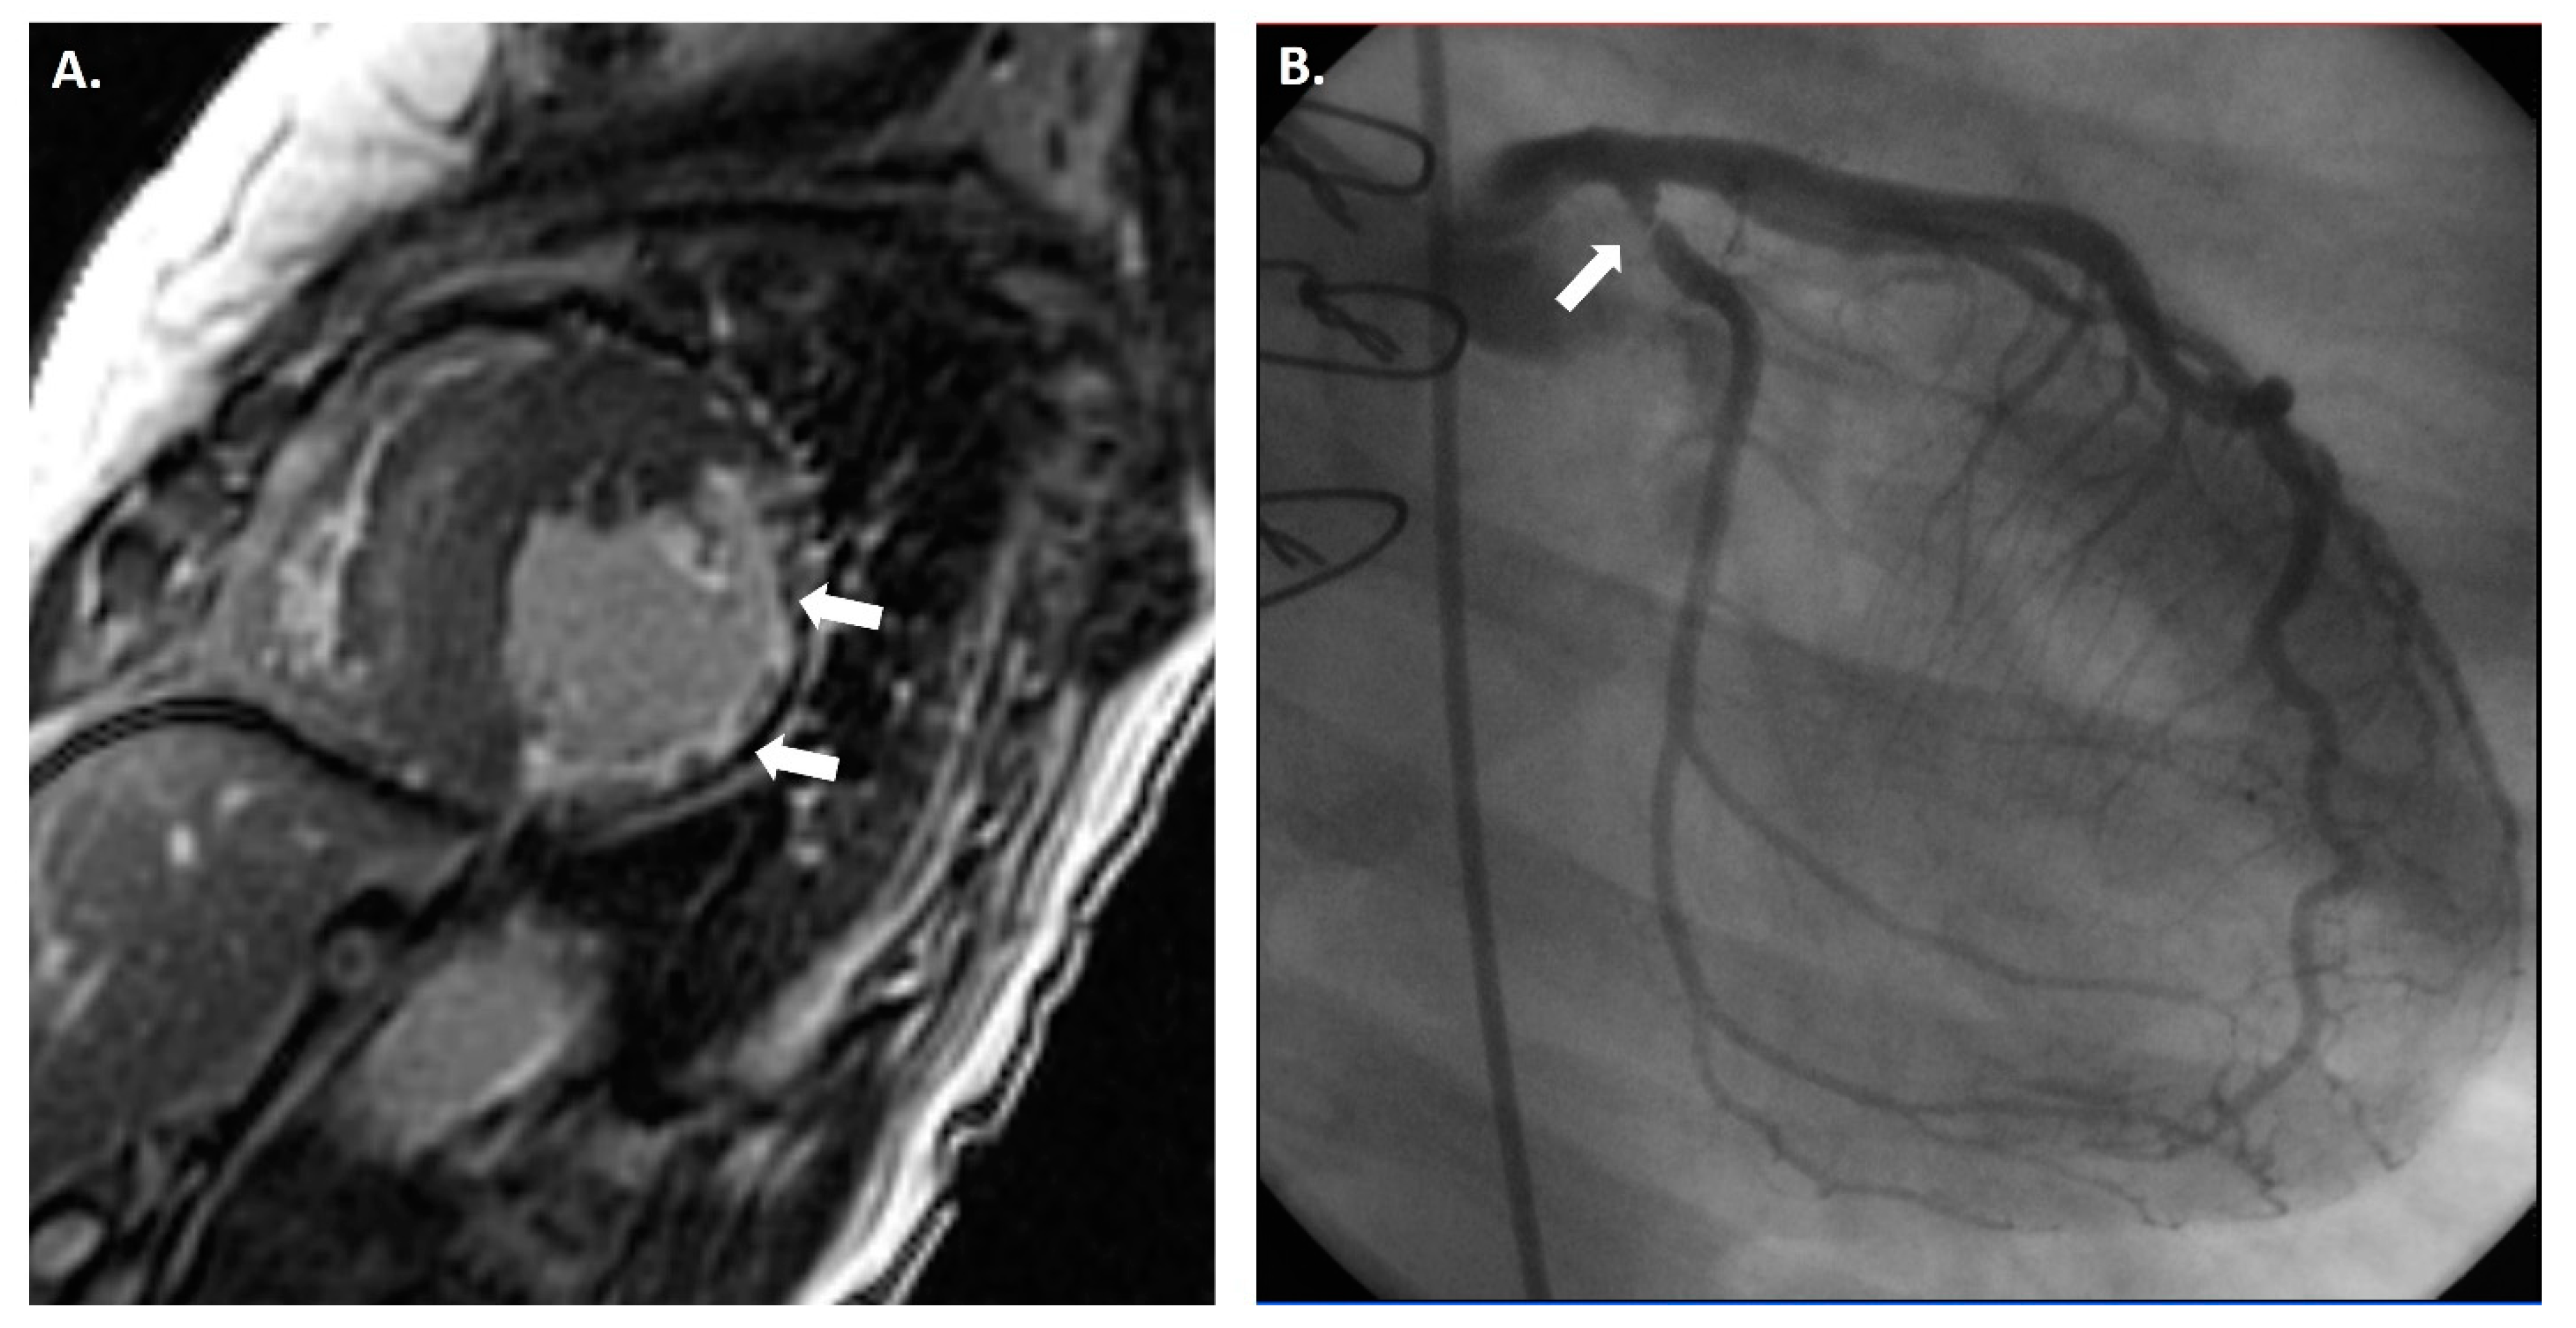

Cardiac magnetic resonance imaging (CMR) is a non-invasive imaging modality that can provide comprehensive information about the structure and function of the heart that is relevant for the diagnosis and prognosis of CAV (Figure 3) [8]. CMR can provide information about structural changes by measuring parameters such as extracellular volume (ECV) fraction, fibrosis, and edema [58]. However, functional parameters such as myocardial perfusion reserve (MPR), diastolic strain (DS) rate by CMR, and peak filling rate (PFR) carry more importance for CAV diagnosis, as most studies using CMR have focused on MPI and strain imaging [59,60]. Therefore, a multiparametric CMR can safely measure various parameters to detect and grade CAV by assessing the myocardial tissue and function in HTx recipients without exposing them to radiation or iodinated contrast agents [61].

Figure 3.

(A) Cardiac magnetic resonance imaging (CMR) showing clear thinning (white arrows) of the anterolateral, inferolateral, and inferior mid-cavity, with subendocardial delayed enhancement in these regions suggesting a vascular etiology. The hypertrophy of the septum is profound but is presumably compensatory due to the extensive loss of lateral wall myocardium. While this CMR finding could be multifactorial, invasive coronary angiography showed a severe obstruction (white arrow) in the proximal circumflex artery (B).